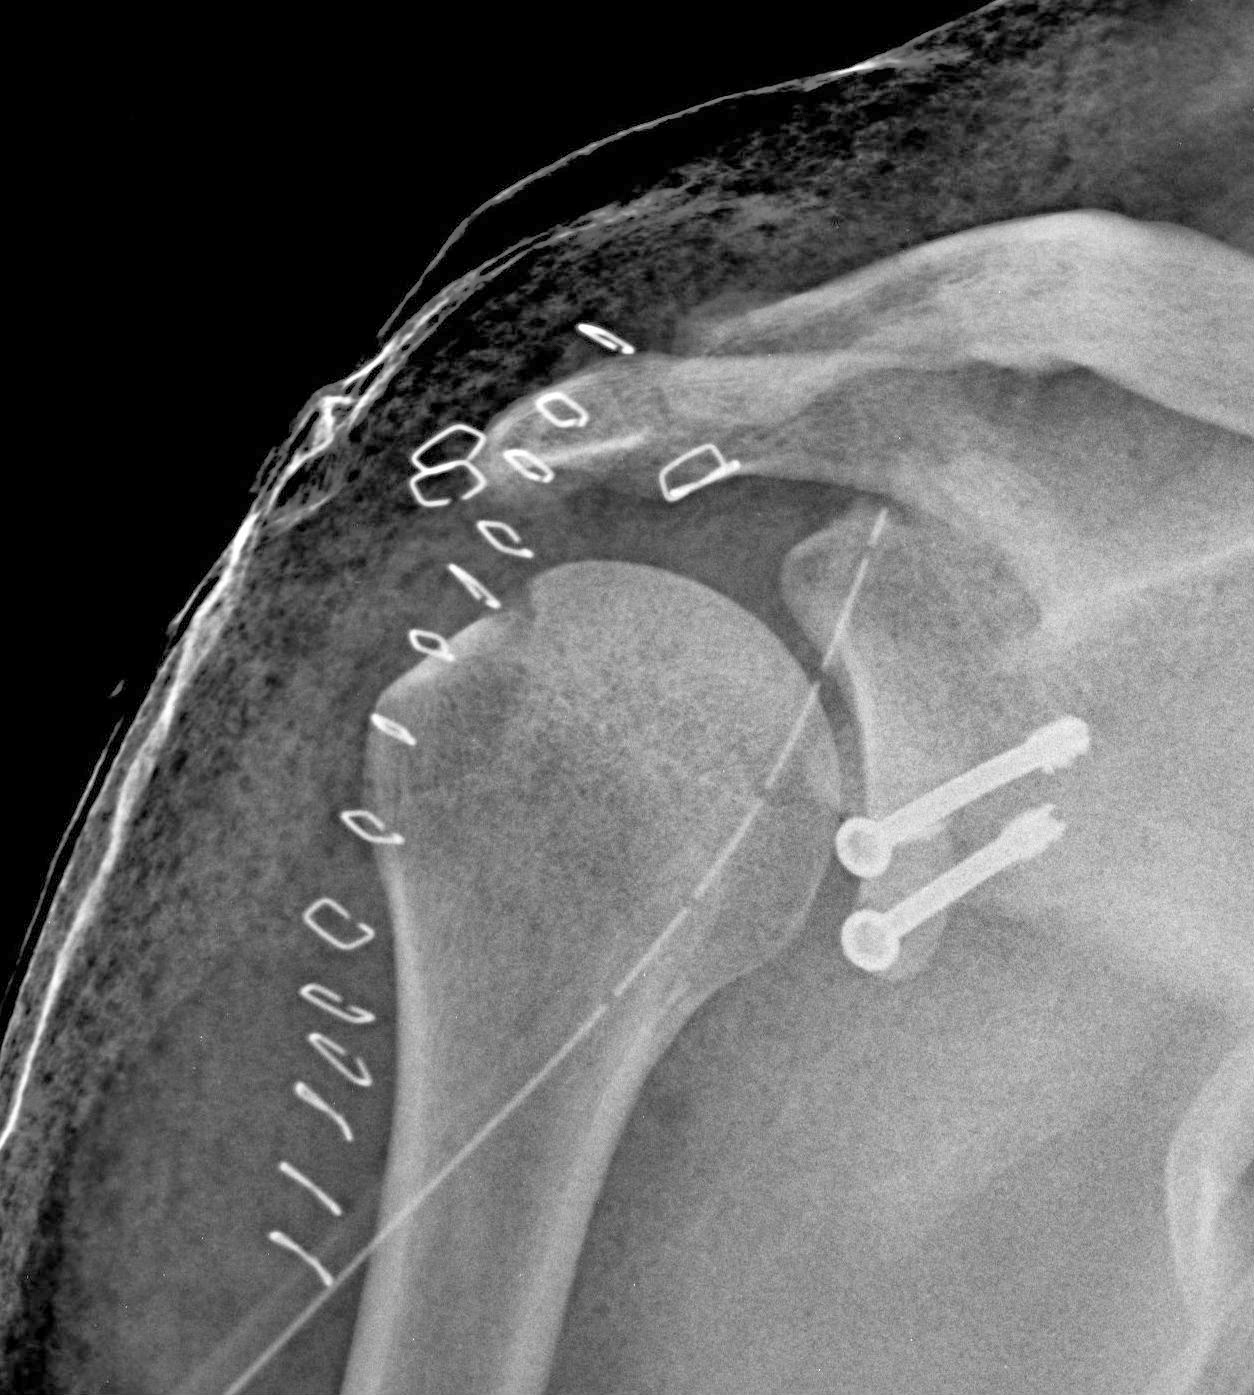

Omuz Kiriklari Op Dr Taner Bekmezci